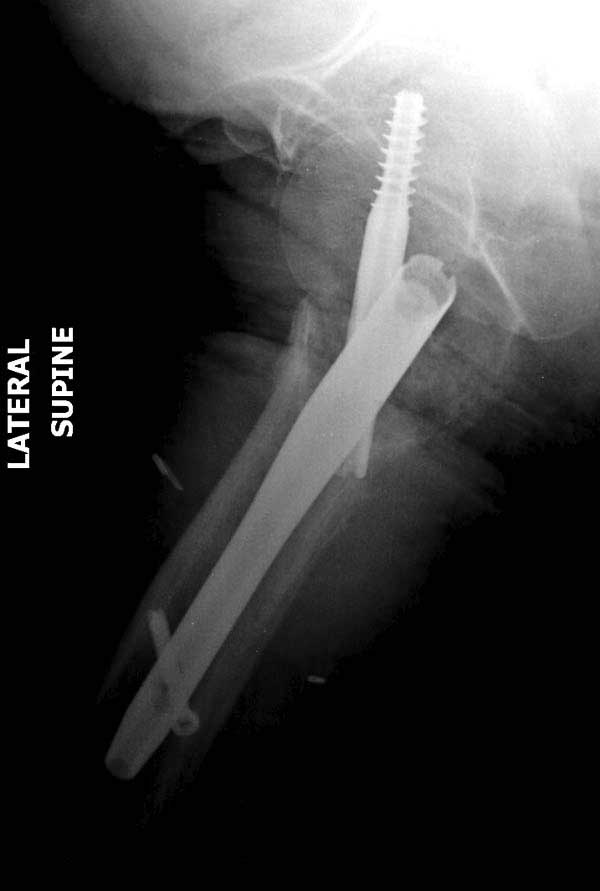

Банальный рутинный перелом чрезвертельной зоны лечимый DHS.

А по картинке можно сказать, что вроде бы все и неплохо. Предупредить миграцию шеечного винта при наружной ротации диафиза во время ходьбы достигают введением последнего поближе к переднему кортексу шейки. На Вашей картинке винт "смотрит" кзади. Отсутствие дополнительной боковой опоры для винта создает предпосылки для несостоятельности фиксации. (См. статью в прикреплении). Поэтому с ранней активизацией пациента в данном случае я бы подождал.

А пациент-то какой из себя?

При таком переломе мы бы тоже поставили вертельный гвоздь - на следующий день встать и побежать - чем не перспектива? На прямом снимке винт стоит замечательно, а коварный аксиальный подкачал, хотелось бы больше по центру шейки и головки завести. Да и смещение, какое-никакое, но есть. Посему - нагрузка 15 кг, а расширяли бы не раньше, чем через 5 недель.

Что касается данного перелома, то по-моему DHS или гамма - принципиальной разницы здесь конкретно нет - медиальная опора сохранена, при правильном исполнении можно ногу нагружать. Технически здесь выполнено на 3+, но если так же винт гаммы поставить - лучше не было бы.

Прилагаю снимок сделанный еще в стационаре через 2 недели после операции.

Первые снимки показывают технические погрешности установки DHS. Не была достигнута репозиция, конечность в флексии и шейка в ротации. Сегодня все меньше обращают внимание на параметры для оценки репозиции (S контуры Lowell в обеих проекциях и Garden Alignment Index, в норме 155 и 180 градусов), хотя такие простые тесты помогли бы дорепонировать смещение. Винт находится сзади в головке, что при нагрузке поменяет вектор и вместо компрессии в линии перелома срежет головку-Cut Out!

В зависимости от дистанции линии перелома и латерального кортекса надо использовать разной длины barrel, т.е. конец баррели не должен доходить до пределов перелома. Здесь конец длинного ствола упирается в медиальный фрагмент, что мешает созданию компрессии, а более короткий barrel создал бы запас для компрессии. В боковой пластине вместо 4х можно было ограничится двумя шурупами, потому что головка шурупа в 4.5 мм выдерживает давление до 350 кг.